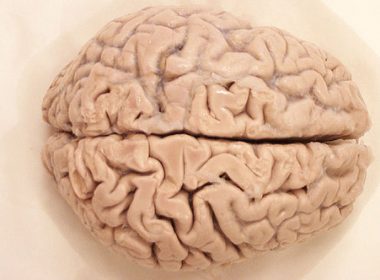

Anatomia mózgu (wykład Tomasza Cecota)

Dziś polecamy jedną z wielu prezentacji na temat anatomii człowieka autorstwa dr. Tomasza Cecota z Centre for Learning…

12/01/2010